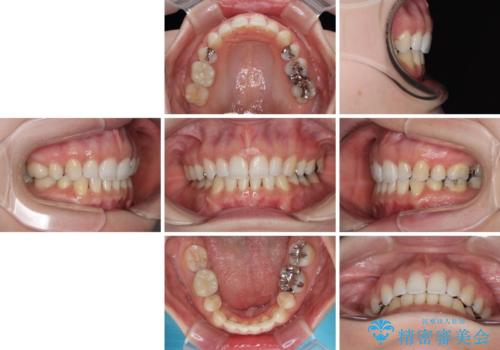

顎先に梅干し皺ができる 閉じにくい唇を抜歯矯正で閉じやすく

- 口元の突出感と口の閉じにくさを気にして来院された患者様です。

上下左右第一小臼歯4本を抜歯し、ワイヤー装置にて口元を引っ込めるよう矯正治療を行うこととしました。

奥歯が前方に傾斜していることで深く咬みこむ(ディープバイト)状態であったので、なかなか抜歯したスペースが閉じず、様々な方法でディープバイトを改善しながら治療を進めていくこととなりました。